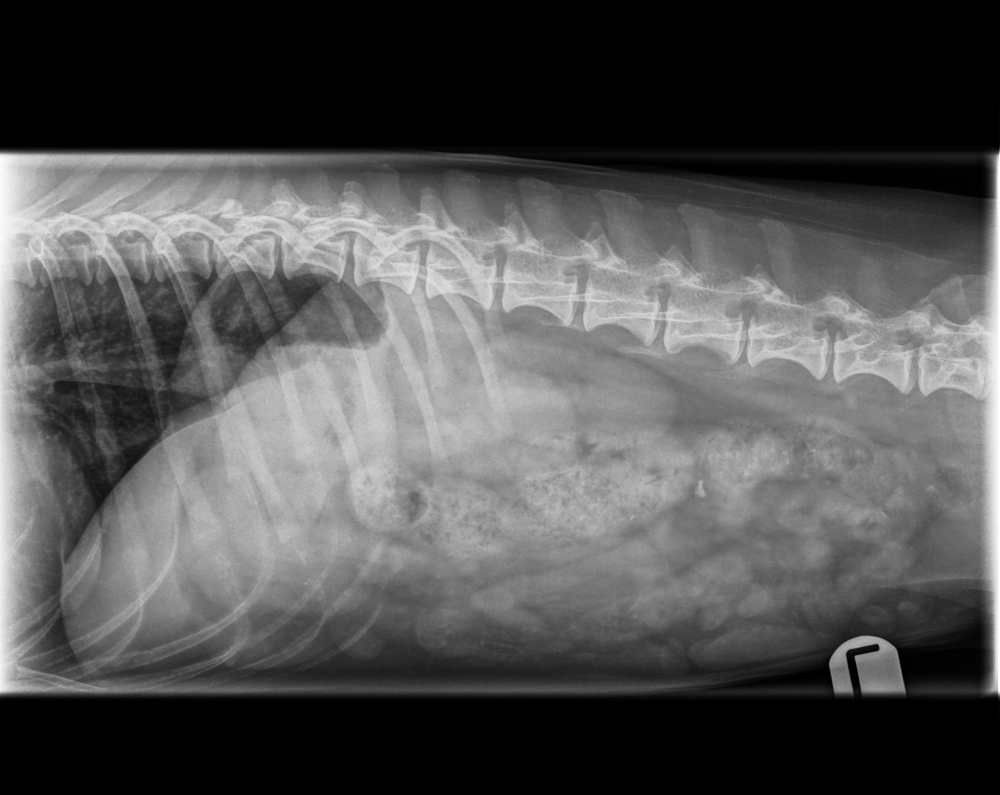

Röntgentutkimus on keskeinen apuväline lemmikin sairauksien ja vaivojen diagnostiikassa. Sen avulla voidaan tutkia luuston lisäksi myös sisäelimiä sekä paikantaa esimerkiksi vierasesineitä ruoansulatuskanavasta. Röntgen täydentää erityisesti sisätautien tutkimuksia silloin, kun oireiden syy ei selviä pelkästään kliinisellä tutkimuksella tai laboratoriokokeilla.

Tarjolla on sekä virallisia että muita diagnostisia röntgentutkimuksia. Virallisiin tutkimuksiin kuuluvat lonkka-, kyynär- ja selkäröntgenkuvaukset. Lisäksi röntgeniä käytetään muun muassa ontumatutkimuksissa sekä rinta- ja vatsaontelokuvauksissa, esimerkiksi sisäelinsairauksien, hengitystieoireiden ja vatsavaivojen selvittelyssä.

Sisätautien selvittelyssä röntgentutkimus yhdistetään usein muihin tutkimuksiin, kuten veri-, virtsa- ja ulostenäytteisiin sekä tarvittaessa ultraäänitutkimukseen. Yhdistämällä eri tutkimusmenetelmiä saadaan mahdollisimman kattava kokonaiskuva lemmikin terveydentilasta ja voidaan suunnitella tarkoituksenmukainen jatkohoito tai seuranta.